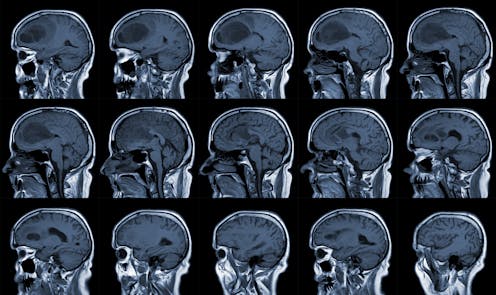

Glioblastoma is the most common and deadliest form of brain cancer. Patients face a bleak prognosis – the average survival after diagnosis is between 12 and 15 months. And just 6.9% of patients survive beyond five years, making it one of the most poorly survived cancers.

Glioblastoma is a naturally occurring tumour that belongs to a group of brain tumours called “gliomas” that originate and grow in the brain and spinal cord. Classified as a grade 4 tumour by the World Health Organization, glioblastoma is one of the most aggressive forms of cancer.